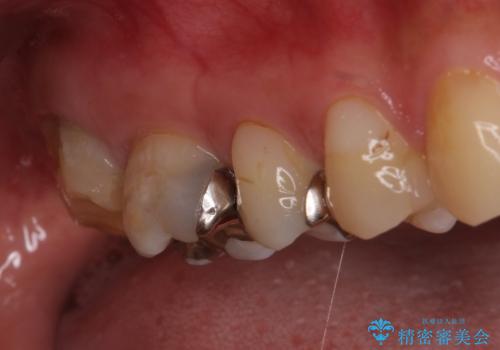

下顎の奥歯は強い痛みを感じており、既に歯髄に不可逆的な炎症が起きていると診断されたため、根管治療の後にセラミッククラウンにて補綴治療を行うこととしました。

下顎のむし歯は歯肉の中にまで及んでいたため、一部歯槽骨を削除し、歯肉縁上に健全歯質が位置するよう外科処置を併用しました。